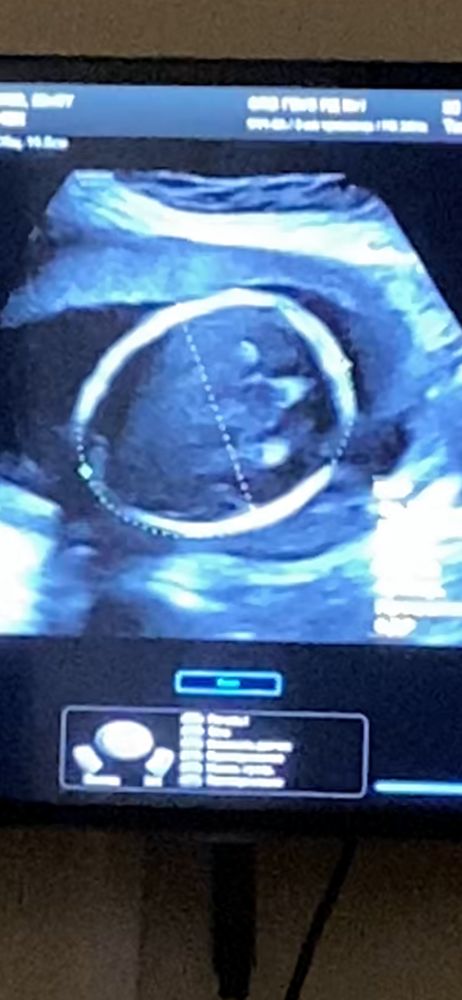

делаем узи из-за шейки раз в 10 дней и постоянно окружность головы отстаёт на неделю где то 🥹 то ставят 14% процентиль, то 35% процентиль, но всегда отставание. При этом БПР - ровно совпадает со сроком. Отстаёт только окружность и от лба до затылка. Я смотрю по форме головы малыша - вроде нормальная голова, не круглая как тыковка, а овал.

вот, например, данные последнего узи в 27 недель :

бпр - 70 мм (80% процентилей)

От лба до затылка - 82 мм (13% процентилей)

окружность головы - 243 мм (14% процентилей).